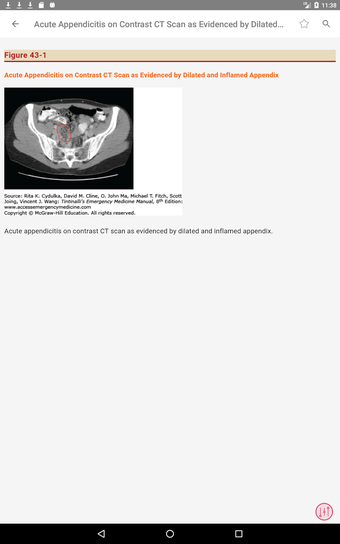

最初に知っておくべきことは、ティンティナリの緊急医療マニュアルが緊急医療の最も重要なトピックについてすべてを提供する包括的なガイドであることです。これは、医師、看護師、および救急医療技師にとって理想的なアプリです。

この無料アプリには、日常の実践に役立つ多くの情報が含まれています。このアプリでカバーされるトピックは、疾患から薬剤、さまざまなタイプの傷害まで幅広く、患者ケアを担当する人々にとって素晴らしいリソースです。